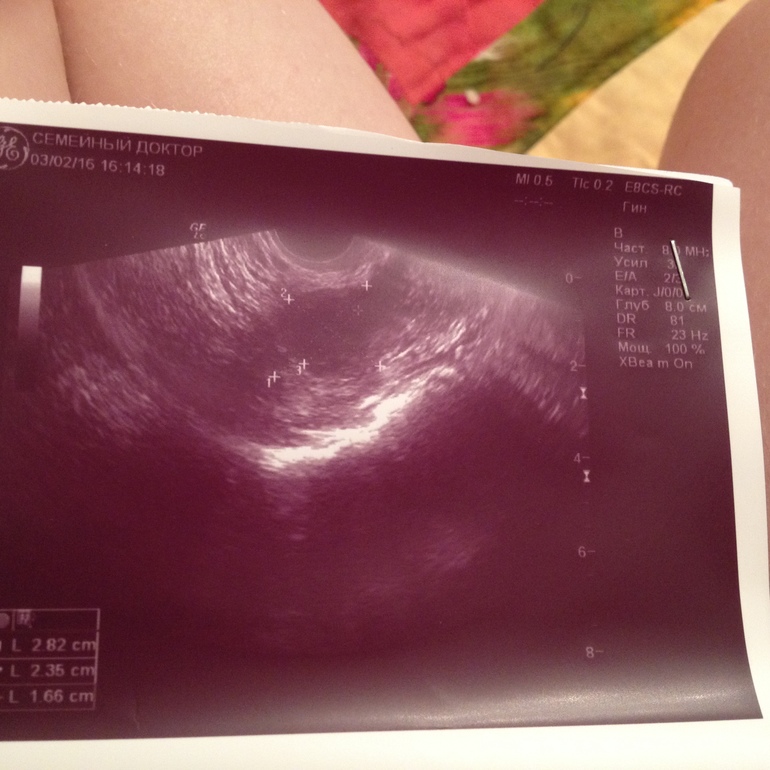

Это был фолик или ЖТ?

На 10 ДЦ была у врача, она сказала что фолликул 16,6. Если это был фолик, то как могут быть сейчас М.

Посмотрите, пожалуйста, фото с узи, м.б. это все-таки ЖТ было и О была в прошлые М?

Немного высвечено фото, в реале фолик более темный. Но мне он кажется неровным все же.